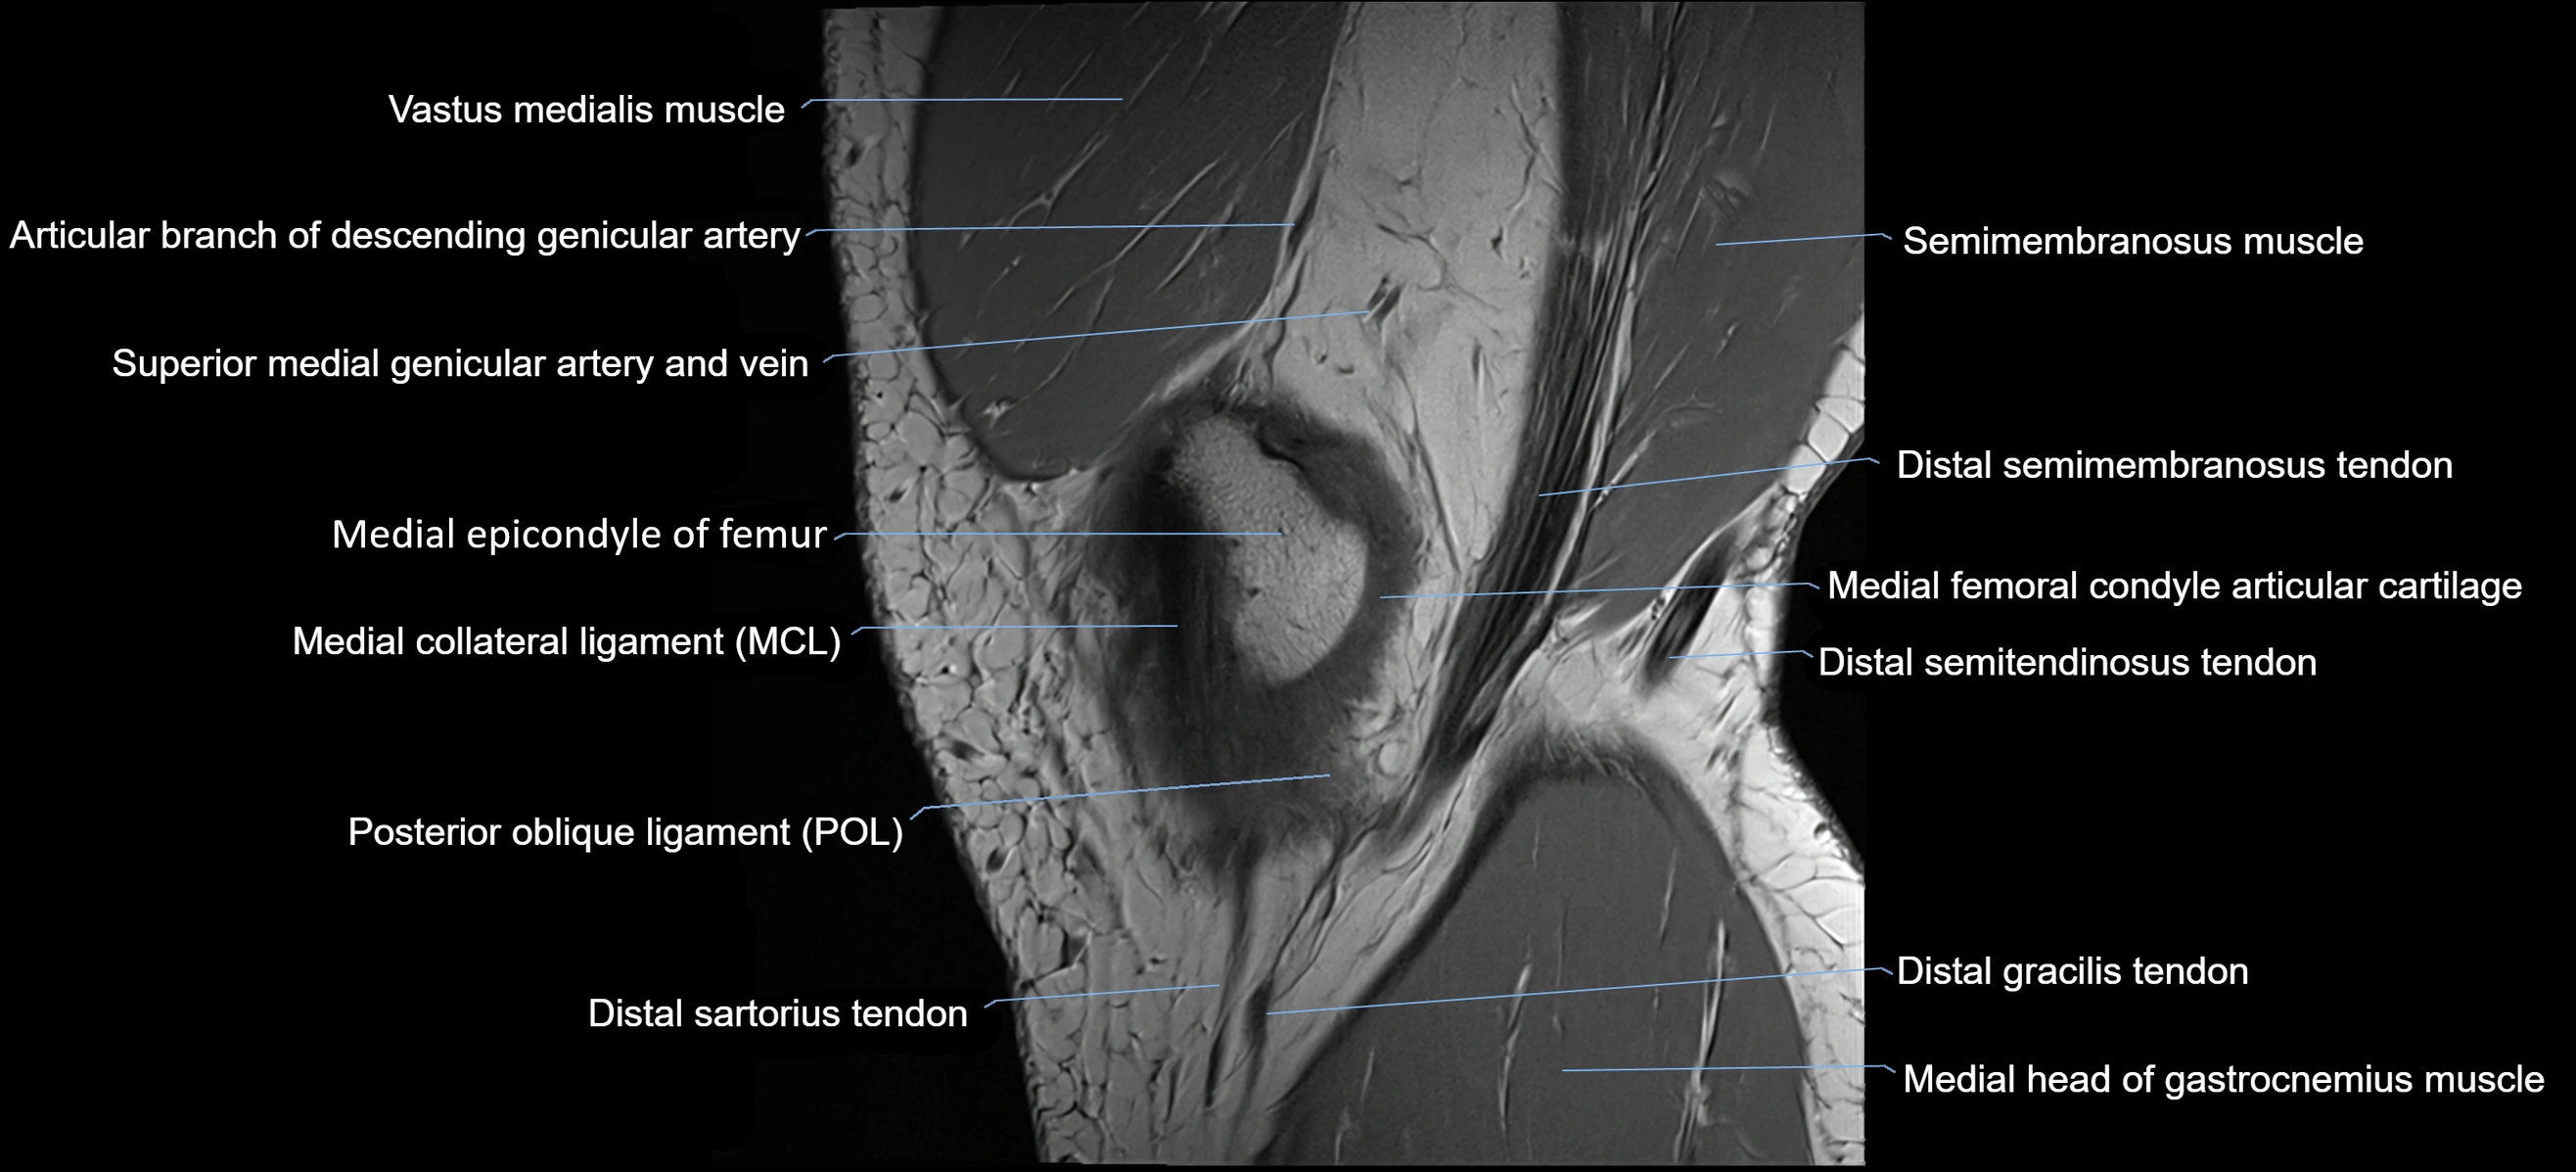

- Descending genicular artery (Articular branches)

- Distal adductor magnus tendon

- Distal semimembranosus tendon

- Distal semitendinosus tendon

- Gracilis tendon (Distal)

- Medial collateral ligament

- Medial epicondyle of femur

- Medial gastrocnemius tendon

- Medial head of gastrocnemius muscle

- Sartorius tendon (Distal)

- Semimembranosus muscle

- Superior medial genicular artery

- Superior medial genicular vein

- Vastus medialis muscle